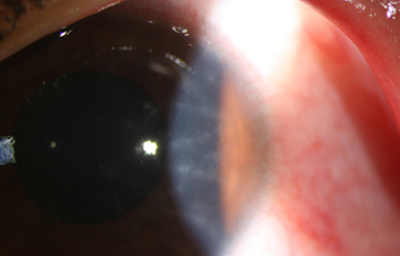

Superficie corneal irregular y grisácea, (Fig. 1, 2) con opácidades granulares en parche y formación de líneas epiteliales elevadas de aspecto granular (Fig. 3), que pueden arborizar dando imágenes de pseudodendritas. Opacidades superficiales satélites. (Figura 4) Inyección ciliar. Ulceración epitelial variante. (Figura 5).

Estas lesiones progresan con la aparición de infiltrados estromales anteriores difusos o focales, (Figura 6) edema circunscrito, y en ocasiones infiltrados en los nervios corneales (Figura 7), (perineuritis, usualmente entre las 1 a 4 semanas de evolución).

Ante la sospecha por los antecedentes e imágenes biomicroscópicas de una queratitis por Acantamoeba, debe hacerse su confirmación diagnóstica mediante extendidos de la superficie corneal para estudio microscópico, con las imágenes obtenidas “in vivo” con microscopía confocal (Figura 31 y 32) y mediante cultivos del parásito.